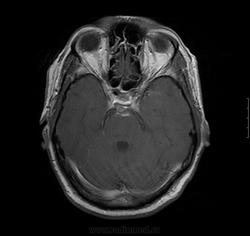

3.06.12 больному выполнена КТ без контраста, заподозрено подкравливание из аневризмы бифуркации базилярной артерии, либо ее тромбирование. Рекомендовано проведение СКТ-АГ.

04.06.2012 проведено СКТ-АГ, выявлено объемное образование ската, спинки турецкого седла с супраселлярным  ростом. Небольшое неоднородное накопление контраста в строме опухоли.

так аневризма то есть или нет? за опухоль наверное могли принять сгусток в предмостовой цистерне, сигнал на Т1 с контрастом и без от предмостовой цистерны одинаков на мой взгляд. МРТ контроль в динамике решит вопрос ИМХО.

Смутил участок кзади от спинки седла по скату гиперинтенсивное на Т2, оттесняющий основную и ЗМА. Переделаю на 3 Тесла